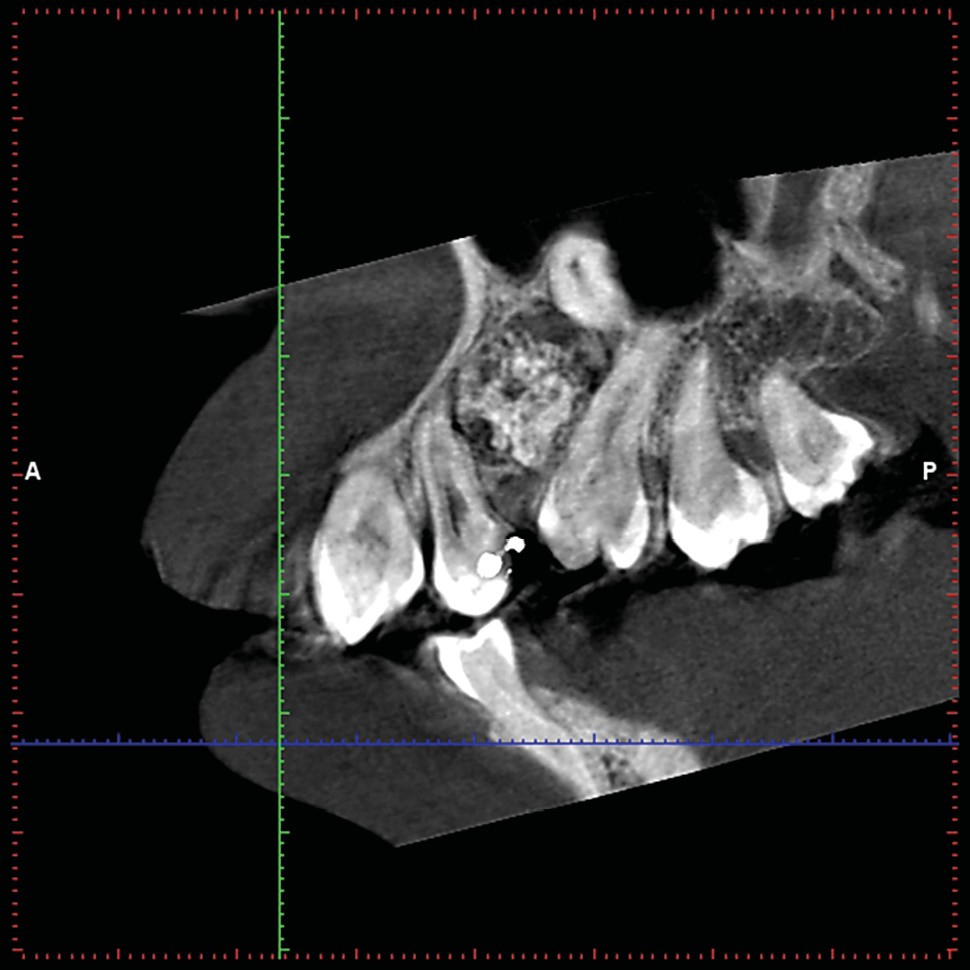

Un CBCT est pratiqué : la périphérie de la lésion ne présente pas de réaction ostéoclérotique (fig. 2) et on retrouve un liseré radioclair « ceinturant » la lésion (fig. 3).